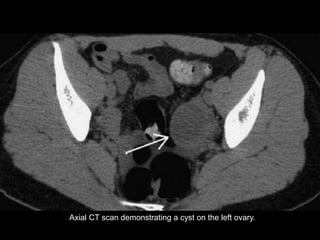

Axial CT scan demonstrating a cyst on the left ovary.

Axial CT scandemonstrating a cyst on the left ovary.